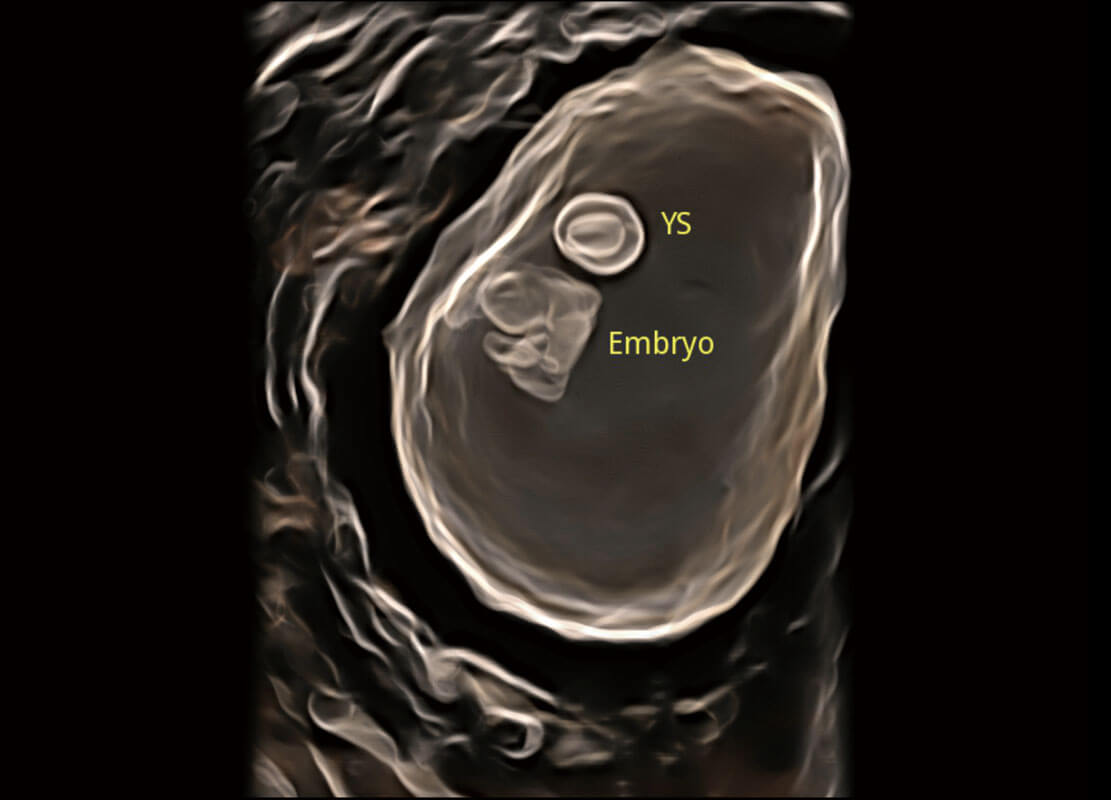

光影成像-孕囊

P60在胎儿早孕期超声筛查中为您带来优异的图像质量。

高分辨率容积成像-早孕胎儿